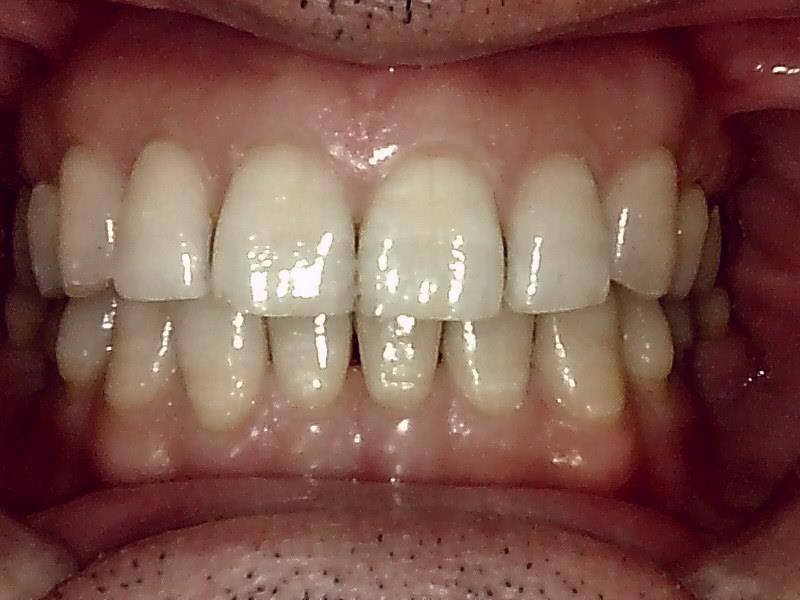

咬合正面観